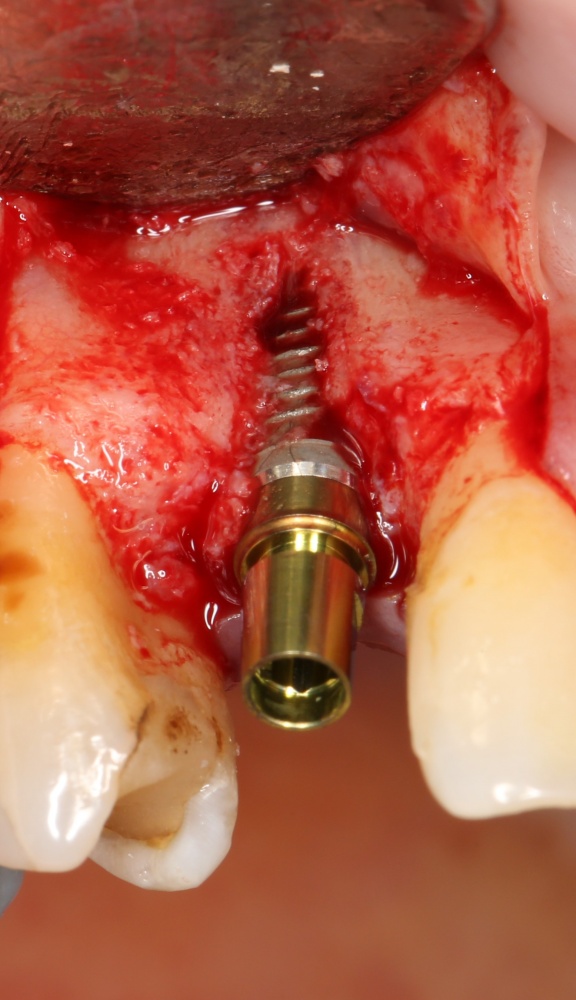

Рекомендации по установке имплантов. Для всех. Часть V.